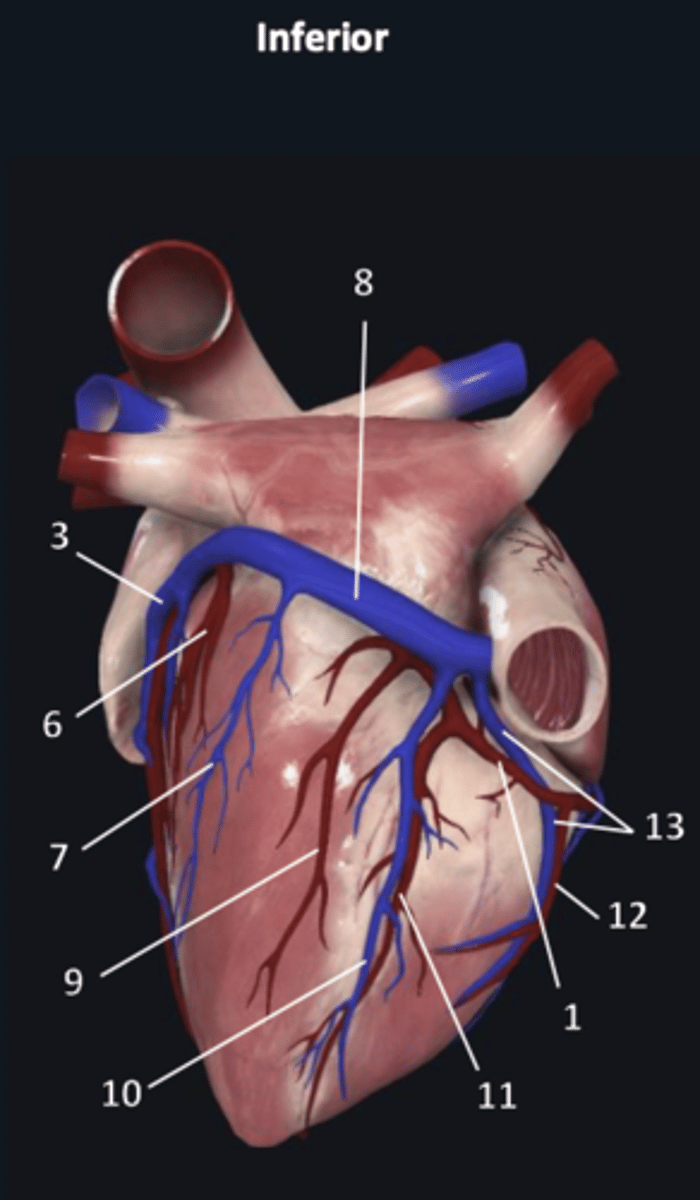

right coronary artery

1

anterior interventricular artery

2 (red)

great cardiac vein

3 (blue)

anterior interventricular artery

2 (red)

great cardiac vein

3 (blue)

left marginal artery

4

left marginal vein

5

posterior left ventricular artery

6

posterior vein of left ventricle

7

coronary sinus

8

right coronary artery

1 (red)

great cardiac vein

3

posterior left ventricular artery

6

posterior vein of left ventricle

7

coronary sinus

8

right posterolateral artery

9

middle cardiac vein

10

posterior interventricular artery

11

right marginal artery

12

small cardiac vein

13